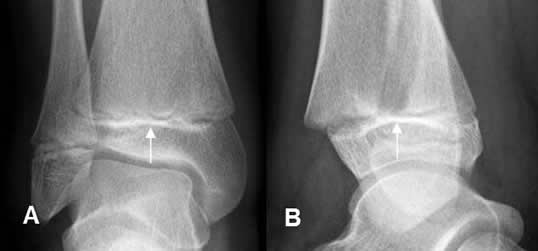

Fig 68 A. Salter tipo I.

A: Rx AP y B: Rx oblicua. Pérdida de la alineación entre la metafisis y la epifisis, por deslizamiento epifisiario tipo I.